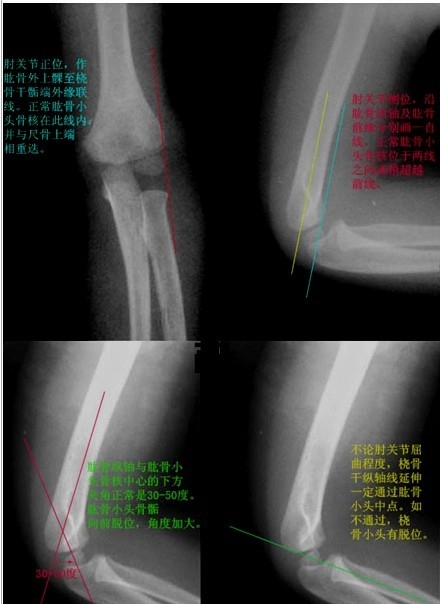

左侧肘关节外侧软组织肿胀明显,外侧髁“双边征”,考虑肱骨外侧髁低位髁上骨折,关节无脱位(桡骨小头连线正常)。

有无脱位战友可以参考下图做连线看看。